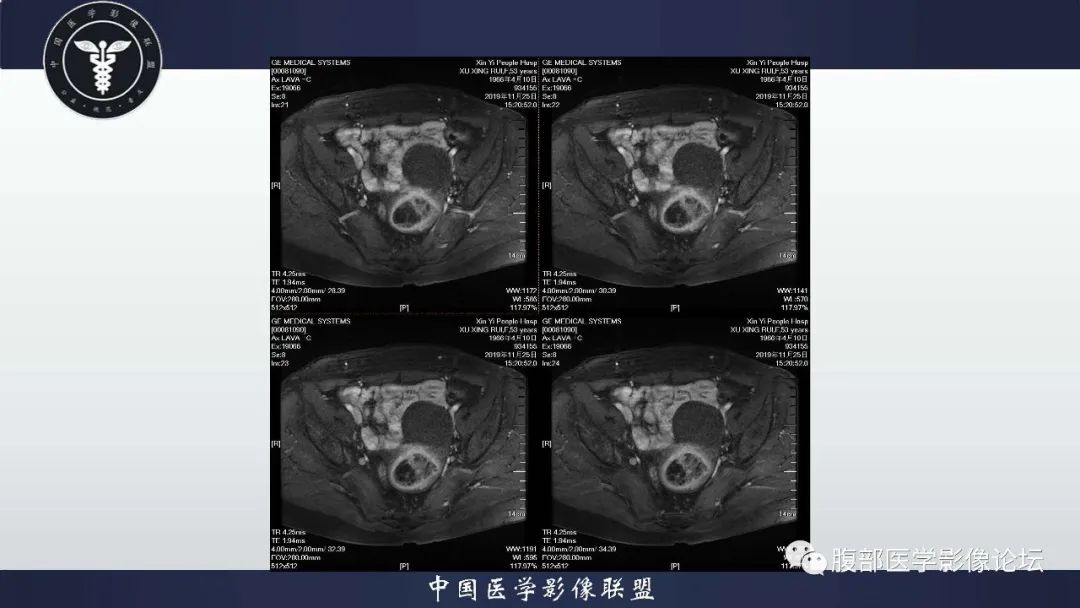

子宫内膜息肉1例MR影像